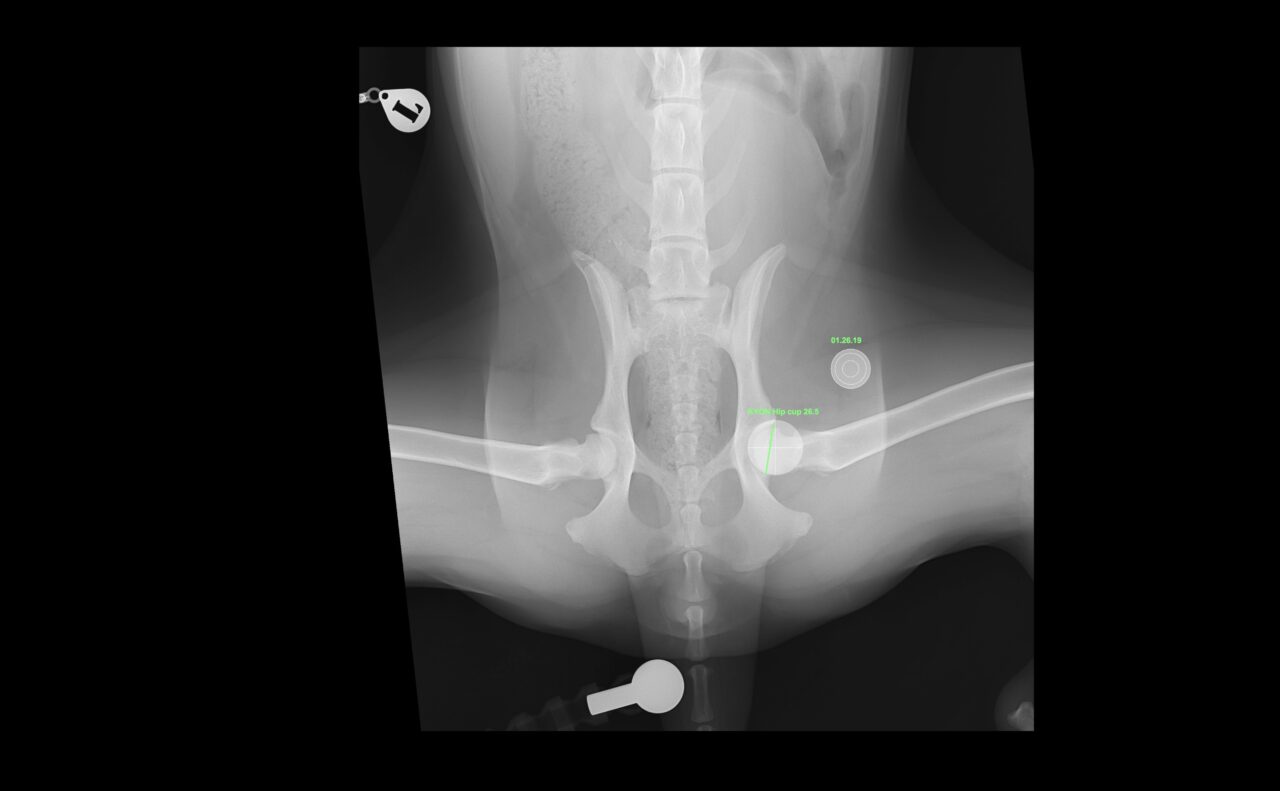

若齢のゴールデン・レトリーバーの股関節形成不全(CHD)に対し、人工股関節全置換術(THR)を実施しました。術前のエックス線では、両側に顕著な股関節亜脱臼を認めましたが、重度の変形性関節症は認められていません。亜脱臼が顕著であることから関節温存のための3Dhip/DPO/TPOは不適応と判断しました。

手術前には vPOP Pro を用いて詳細な術前シミュレーションを行いました。

今回、選択したインプラント

• Acetabular Cup:26.5 mm